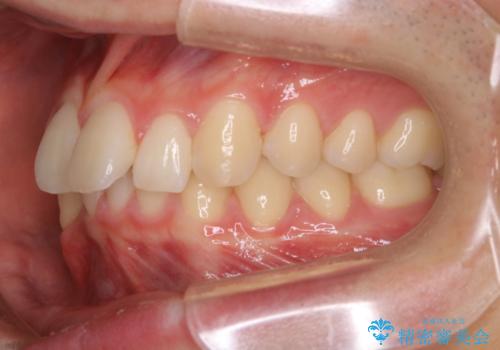

- 口元の突出感は気にならないが、上の前歯の角度と、下の前歯のがたつきが気になるとご相談にいらした方です。なるべく費用や治療期間を抑えて治療したいとのご希望に合わせて治療を計画しました。

この患者様への治療方針として、奥歯から少しずつ歯を移動させる方法と、歯をわずかに削って並べる方法とをご提案しました。短期間での治療を望まれたため、歯をサイズダウンさせて歯を並べました。わずかではあるものの、削った歯は元には戻せないことを十分ご説明し、ご理解ご了承を頂いた上で治療を行いました。